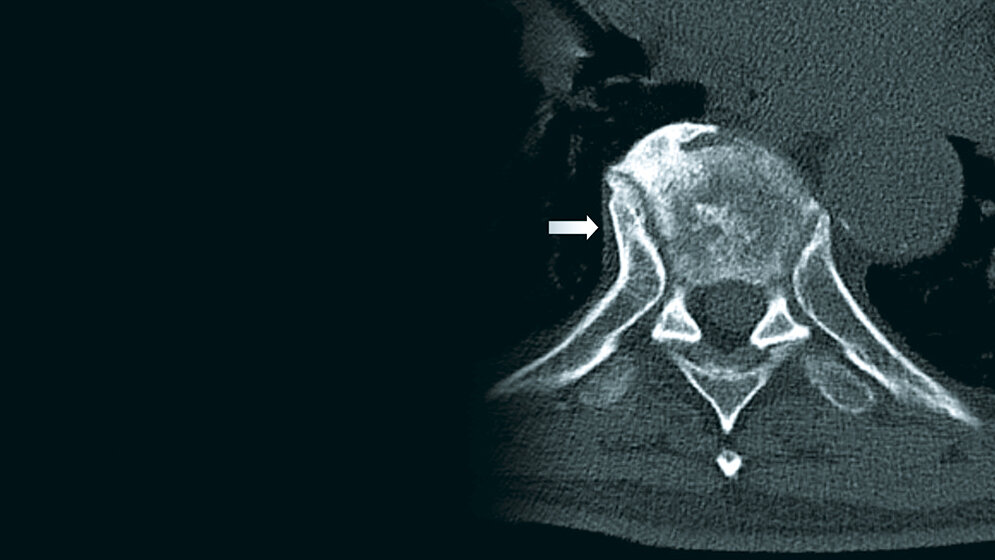

Degenerative Veränderungen: Morbus Forestier

Der Morbus Forestier ist eine krankhafte Veränderung der Wirbel mit ausgeprägten Osteophyten. Bei Patienten mit zunehmender Dysphagie und Schlafapnoe, bedingt durch die Veränderungen beim Morbus Forestier, ist die operative Behandlung eine effektive Therapie. Vermutlich sind verschiedene metabolische Faktoren mit DISH assoziiert. Der hinter der Erkrankung stehende Pathomechanismus ist noch nicht vollständig aufgeklärt.